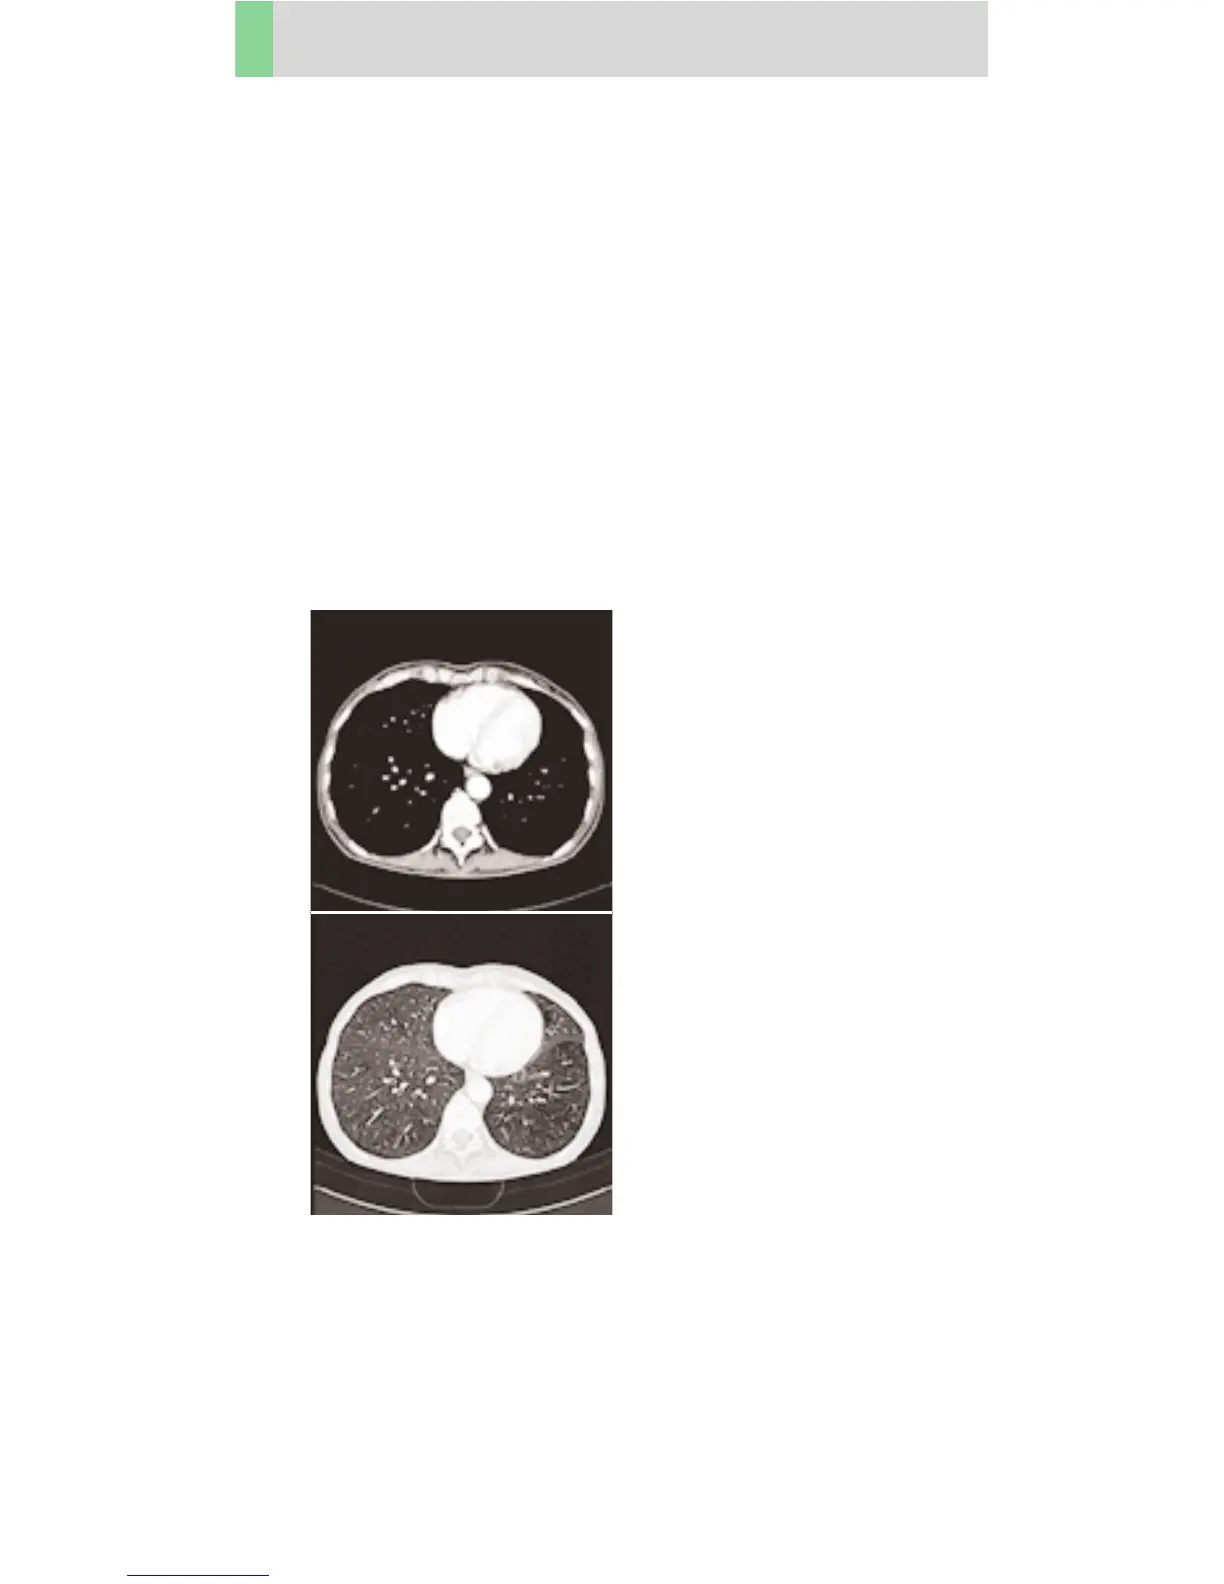

Thorax

ThoraxCombi

Combining thin slice lung and routine thorax studies

with one spiral scan. E. g. thorax studies in general and

interstitial changes in the lungs.

There are two recon jobs predefined. The first one,

with 5 mm slice thickness, for the mediastinum,

the second reconstruction, with 1.25 mm slice thick-

ness for the lung.

A range of 30 cm will be covered in 23.8 sec.